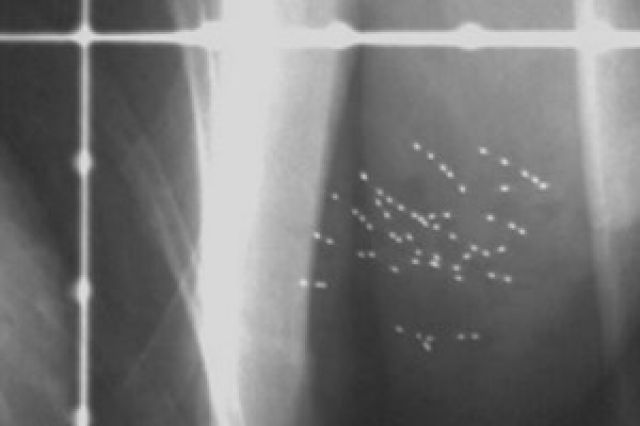

Hạt phóng xạ có thể điều trị tận gốc bệnh ung thư vú

Các chuyên gia điều trị ung thư tại Trung tâm ung thư Tom Baker, thành phố Calgary, Canada đang sử dụng phương pháp mới trong điều trị ung thư vú. Đó là cấy ghép các hạt phóng xạ để tiêu diệt những tế bào ung thư còn lại sau khi mổ bóc tách các khối...